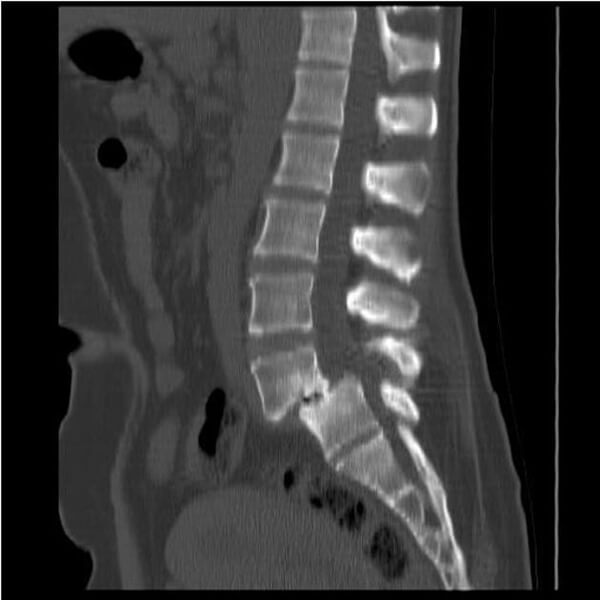

추간판탈출증

추간판탈출증은 추간판이 돌출되어 요통 및 신경 증상을 유발하는 질환이다. 즉, 추간판 내부의 젤리 같은 수핵이 탈출하여 주변을 지나는 척추신경을 압박함으로써 다양한 신경학적 이상 증상을 유발한다. 우리에게 "디스크"라고 잘 알려진 질환이 바로 추간판탈출증이며, 주로 점진적 퇴행과 관련이 있어 정상적인 노화 과정이나 외상에 의해 발생한다.